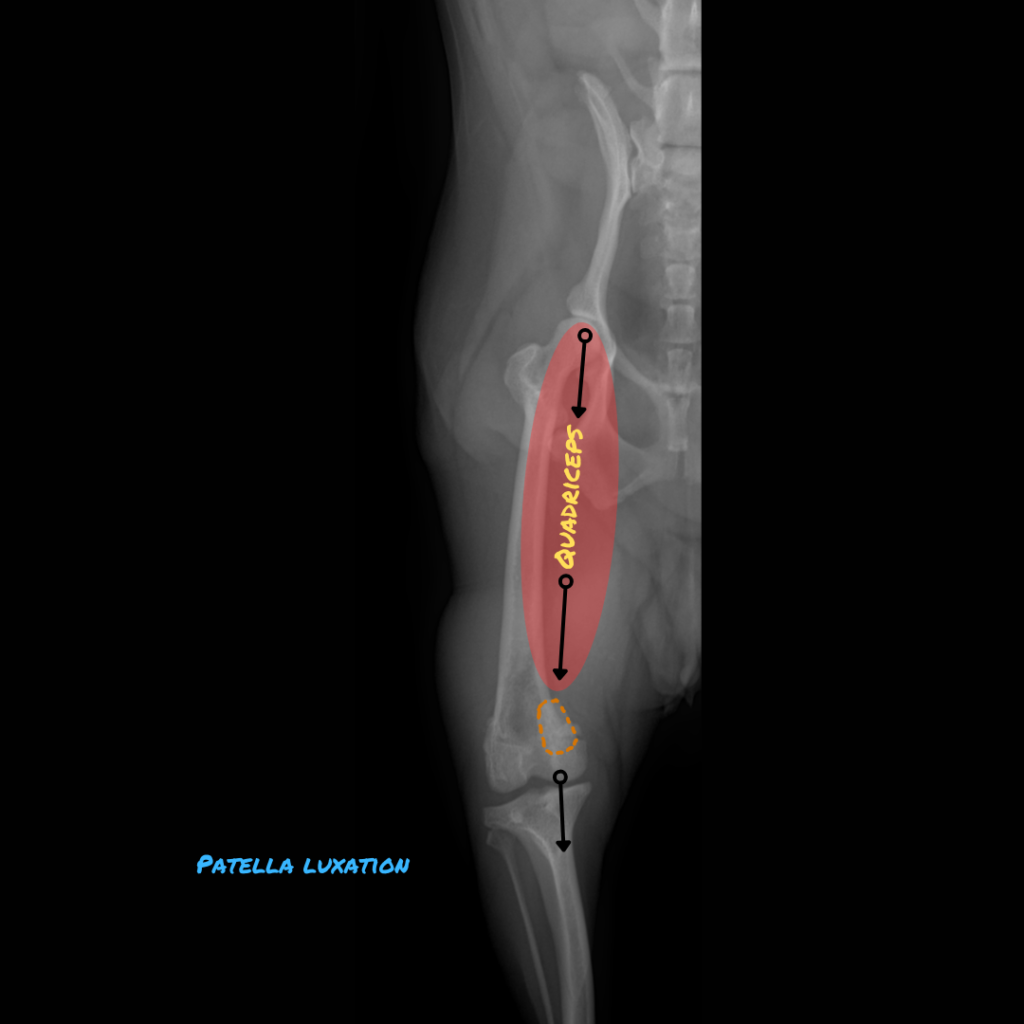

Patellar luxation occurs when the kneecap slips out of its groove, shifting medially or laterally. The patella is embedded within the tendon that connects the quadriceps muscle to the tibial tuberosity, assisting in knee straightening. The patella shields the tendon as it glides over the end of the thigh bone.

As a rule of thumb, dogs with clinical signs associated with patellar luxation of any grade may be considered for surgical correction. Such signs may include persistent lameness or multiple, frequent episodes of lameness. Grade 3 and 4 luxations most frequently benefit from surgery, while grade 2 luxations may also benefit if they meet the above criteria.